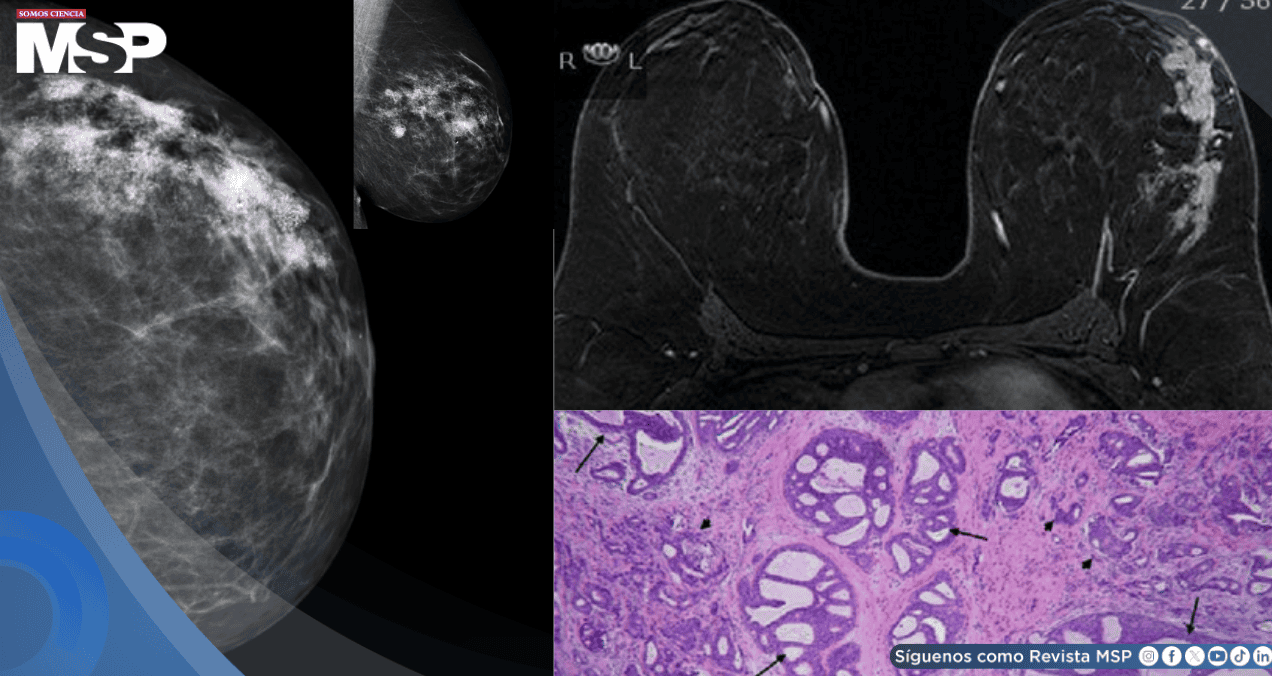

La primera paciente tenía solo 21 años cuando consultó por secreción sanguinolenta espontánea en su pezón izquierdo. Durante años había mantenido su celular en el lado izquierdo del sostén varias horas diarias. Los estudios revelaron un carcinoma ductal extenso con microinvasión multifocal que abarcaba 12 centímetros, requiriendo una mastectomía.

Otra mujer de la misma edad descubrió una masa palpable en su seno izquierdo, justo en el punto de contacto con el dispositivo. Llevaba seis años usando su celular en el sostén ocho horas o más cada día. El análisis post-mastectomía mostró cáncer invasivo multifocal con metástasis en ganglios linfáticos. Posteriormente, desarrolló metástasis óseas.

El tercer caso corresponde a una mujer de 33 años que presentó dos masas palpables en el cuadrante superior externo de su mama derecha, directamente bajo donde colocaba el teléfono mientras corría. Usaba una aplicación GPS durante sus entrenamientos. La resonancia magnética detectó al menos seis lesiones sospechosas distribuidas a lo largo de 8 centímetros.

La cuarta paciente, de 39 años, tenía tres masas en el área de contacto con el teléfono en su seno derecho. Durante una década, había usado el dispositivo en su sostén mientras trabajaba, empleando un manos libres Bluetooth para conversar durante horas cada día. La mastectomía reveló cuatro carcinomas ductales invasivos separados.

Lo más llamativo de estos casos es la similitud en las características patológicas. Todos los carcinomas mostraron una histología casi idéntica, caracterizada por una mezcla de patrones tubulares y sólidos. Todos fueron positivos para receptores de estrógeno y progesterona, pero negativos para Her2.

Las unidades ductales y lobulares alejadas de las áreas de contacto con el teléfono no mostraron cambios histológicos significativos, lo que sugiere que el efecto estaba localizado precisamente en la zona expuesta.